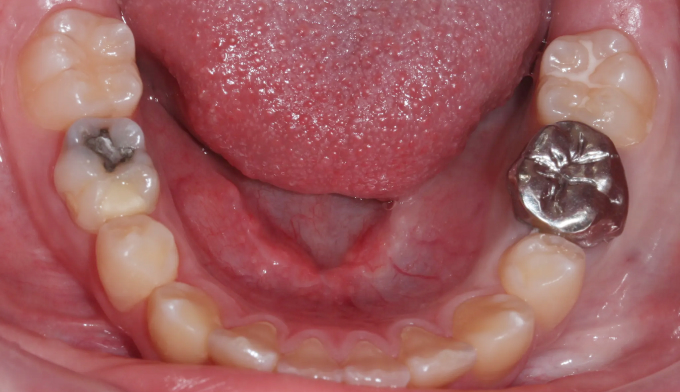

이번 케이스에서는 위쪽 송곳니의 맹출경로이상, 아래쪽 작은어금니는 작은 물혹으로 인해 맹출 경로에 문제가 생겨 교정을 진행한 경우입니다.

물혹을 제거하고 치아 교정장치를 부착하여 간단히 배열하였습니다.

총 교정기간은 11개월 입니다.